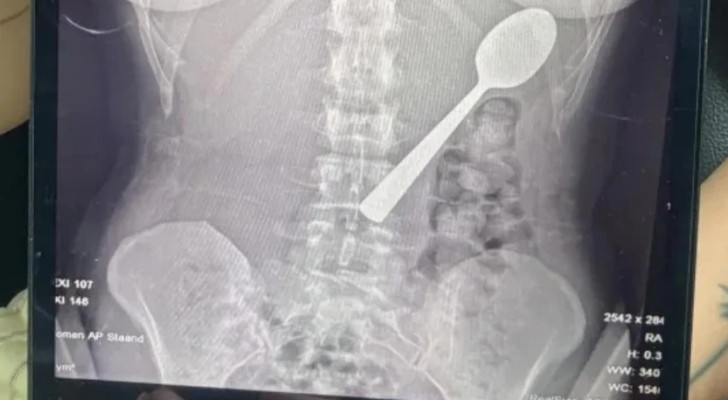

أغرب حالة طوارئ.. امرأة تبتلع ملعقة بطول 17 سنتيمترا عن طريق الخطأ! وهذا ما حل بها

تعرضت امرأة بلجيكية لموقف صادم وغير معتاد، بعدما ابتلعت ملعقة بطول 17 سنتيمترا عن طريق الخطأ أثناء تناولها الطعام، نتيجة قفز كلبها المفاجئ عليها.

ولم تشعر ريمي بحاجة لإخطار شريكها فورا بما حدث، وادعت أن كل شيء على ما يرام، لكن بعد العشاء شعرت بآثار الملعقة داخل جسمها، ما استدعى مراجعة الأطباء. وأوضح الأطباء أن الملعقة كبيرة جدا لتخرج طبيعيا، ما استلزم إجراء منظار للمعدة.

وأزيلت الملعقة بعد يومين تحت التخدير الموضعي، حيث اضطر الأطباء لتدويرها داخل المعدة، ما تسبب في نزيف بسيط. وأكدت ريمي أن الحادث لم يترك أي أضرار دائمة، لكنها عانت من التهاب في الحلق ونزيف طفيف في المعدة وحساسية لبعض الوقت.